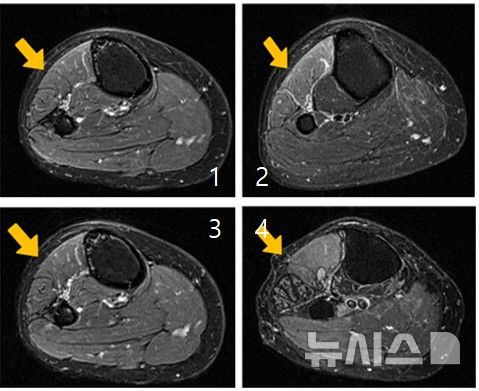

양진서 한림대학교춘천성심병원 신경외과 교수는 발목을 들어 올리는 근력 저하와 함께 무릎 바깥쪽 감각 이상에 주목했다. 이후 무릎 부위 MRI(자기공명영상) 검사를 시행한 결과, 무릎 외측을 지나는 비골신경이 섬유성 구조물에 의해 압박돼 있는 것을 확인됐다. 양 교수는 조씨의 증상을 ‘비골신경병증에 의한 족하수’로 진단했다. 족하수는 발목과 발가락을 들어 올리는 힘이 약해지는 증상으로, 걷거나 계단을 오를 때 발끝이 바닥에 끌리거나 발을 제대로 들지 못하는 것이 특징이다.

양진서 교수는 “뇌와 척추 MRI 검사에서 이상이 발견되지 않는데도 발목이 들리지 않는다면, 말초신경병증 가능성을 반드시 고려해야 한다”며 “비골신경병증은 무릎 부위 MRI만으로도 비교적 명확한 진단이 가능한 질환이지만, 질환에 대한 인식이 부족하면 불필요한 검사와 치료로 시간을 허비하게 된다”고 지적했다.

비골신경병증의 치료는 증상 발생 초기에는 발목 보조기 착용, 소염진통제 등 약물치료, 물리치료와 같은 보존적 치료를 우선 시행한다. 이러한 치료로 증상 호전을 기대할 수 있으나, MRI 검사에서 비골신경 주행 부위의 압박이 명확하게 확인되거나 일정 기간 보존적 치료에도 불구하고 족하수 증상이 지속·악화되는 경우에는 수술적 치료를 고려하게 된다.